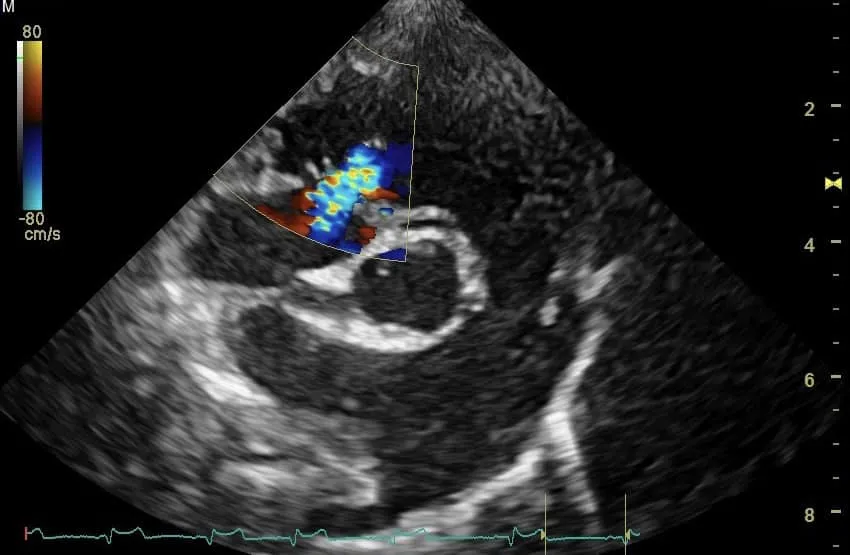

🫀第三步: 心臟超音波/心電圖檢查,診斷左右心房嚴重擴張、二尖瓣與三尖瓣逆流與肺高壓問題。

🫀第三步: 心臟超音波/心電圖檢查,診斷左右心房嚴重擴張、二尖瓣與三尖瓣逆流與肺高壓問題。